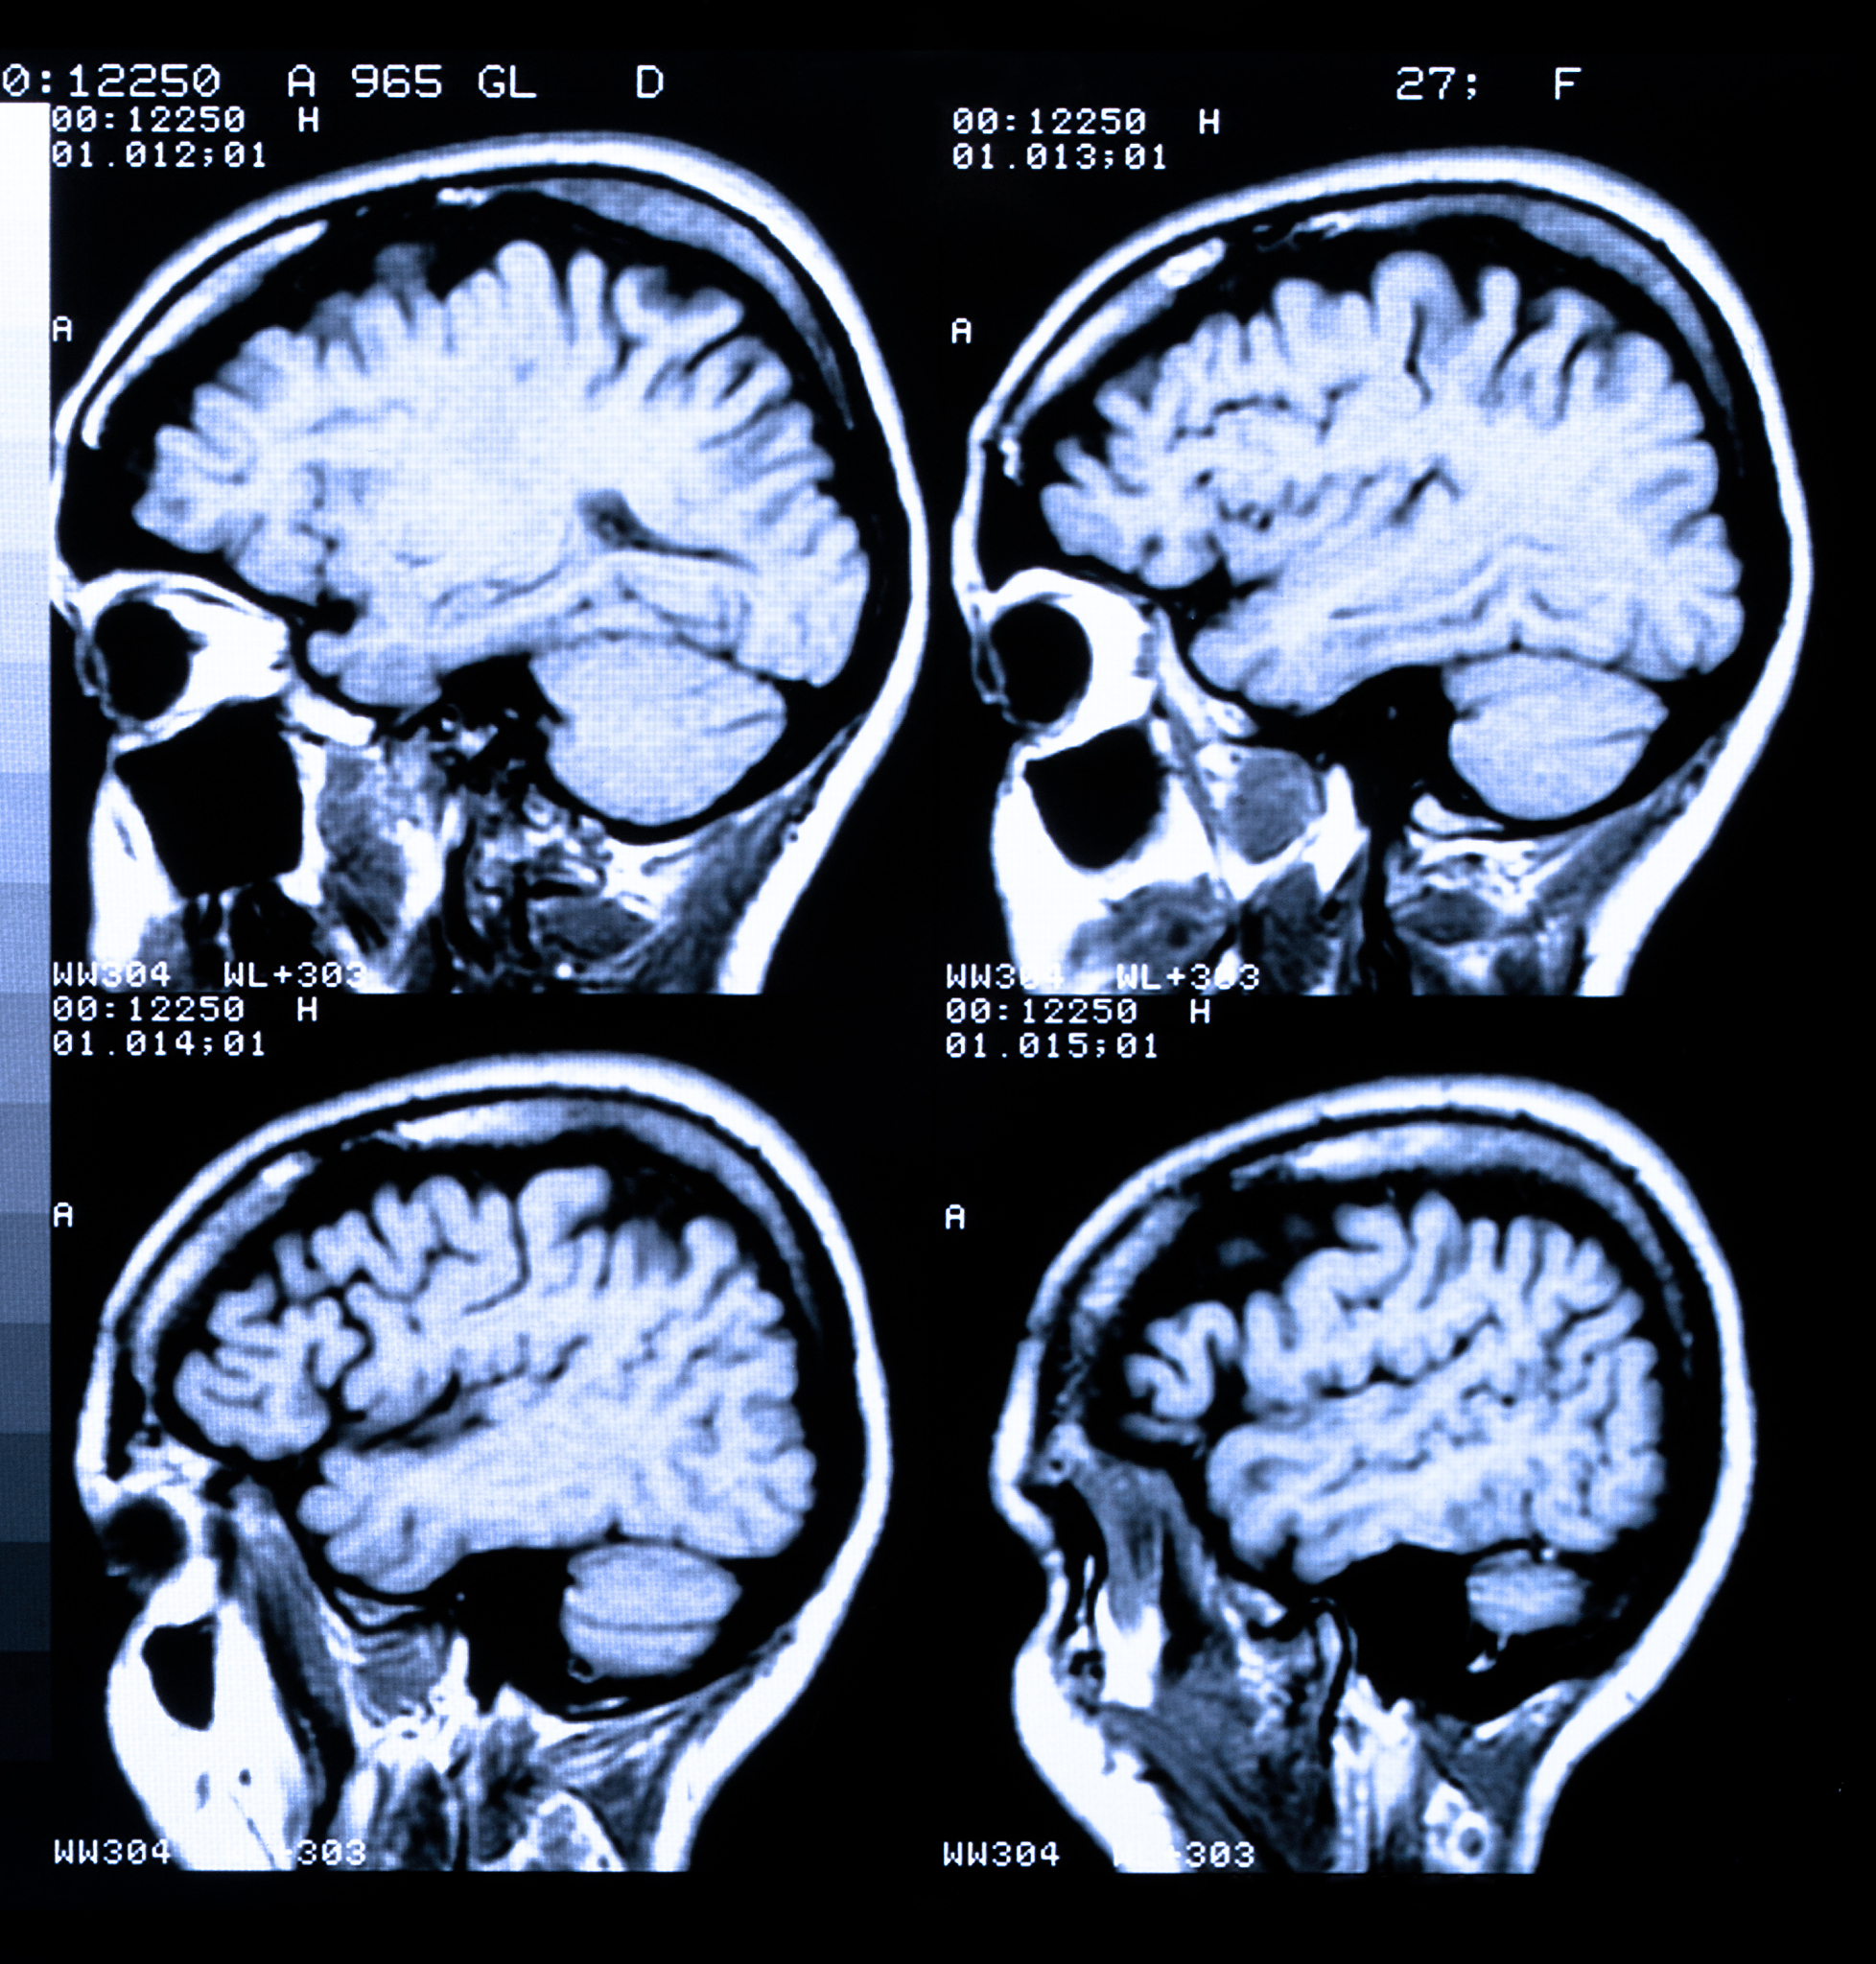

脑出血和单纯疱疹性脑炎是两种不同的疾病,它们之间没有直接的相关性。脑出血是指脑血管破裂导致出血,可能是由于脑动脉瘤破裂、高血压引起的脑出血等原因。而单纯疱疹性脑炎是由单纯疱疹病毒感染引起的一种病毒性脑炎。

尽管脑出血和单纯疱疹性脑炎没有直接的相关性,但两者都可以导致严重的神经系统损伤和致命后果。脑出血会导致脑组织受损,压迫周围结构,引起神经功能障碍。而单纯疱疹性脑炎会导致病毒在脑组织中繁殖,引起脑炎症状,如头痛、发热、意识障碍等。

在某些情况下,脑出血和单纯疱疹性脑炎可能同时存在于同一个患者身上,但这种情况相对较少见。如果同时发生,可能会增加患者的病情严重程度和治疗难度。

总之,脑出血和单纯疱疹性脑炎是两种不同的疾病,但它们都会对神经系统造成严重的损害,需要及时诊断和治疗。